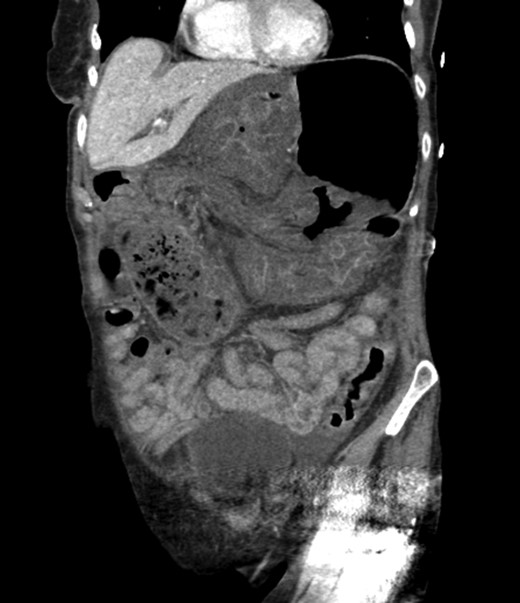

An 81-year-old female with a medical history of CAD with stents, hyperlipidemia, hypothyroidism, GERD, recent UTI, pancreatic cyst, constipation, anemia and leukopenia presented to the ED with a 1 day history of mild, diffuse and cramping abdominal pain. The patient was unable to give an accurate history, but the son at bedside supplemented this reporting that for several years the patient had been experiencing ill-defined abdominal discomfort. Physical exam showed a soft abdomen with mild tenderness and no evidence of peritonitis. A CT scan of the abdomen and pelvis with IV and PO contrast (Fig. 1) showed edematous changes to the mesentery of the small and large bowel with swirling of vessels indicative of internal hernia. The stomach was also noted to be distended with both air and fluid as a consequence of posterior compression by the hernia contents (Fig. 2). A surgical consult was obtained, a nasogastric tube and Foley catheter were placed, antibiotics were started, and the patient was taken for an exploratory laparotomy. Upon entering the abdomen through a vertical midline incision, 1.5 l of ascites was drained revealing a diffusely edematous mesentery. A large portion of the small bowel was seen to be herniated through the Foramen of Winslow (Fig. 3). A Kocher maneuver and division of the gastrocolic ligament were then performed to allow release of the herniated small bowel. It was at this time that, in addition to small bowel, a large portion of the ascending and transverse colon was noted to be herniated through the foramen of Winslow. The small bowel was also seen to be torsed about its own mesentery. Normal anatomy was restored and the bowel noted to be healthy and viable with peristalsis (Fig. 4). Due to the large size of the foramen after reduction and enlargement, it was deemed best to leave it open to prevent any further incarceration or strangulation. The abdomen was closed and the patient tolerated the procedure well. At a follow-up visit 2 months later, the patient had well-healed incisions, was doing well, tolerating a diet, and gaining weight appropriately.

Externalized abdominal contents shown to be pink and healthy bowel with some areas of ecchymosis in the transverse colon.